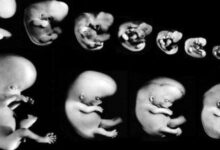

تعتبر فترة الحمل في الشهر الخامس من أكثر الفترات التي ترتاح فيها السيدة الحامل، وذلك بسبب التخلص من أغلب أعراض الحمل المزعجة، ويبدأ توقيت هذا الشهر من الأسبوع الثامن عشر إلى الأسبوع الواحد والعشرين، ويزداد نمو الجنين خلال هذا الشهر بشكلٍ ملحوظ، كما يزداد حجم بطن الأم بالتزامن مع زيادة وزن الجنين وحجمه، وسيتم في هذه المقال عرض التطور في شكل الجنين وحجمه في الشهر الخامس من الحمل.

- الأسبوع الثامن عشر: يصل طول الجنين خلال هذا الأسبوع إلى ما يقارب ال14 سم، ويصل وزنه إلى حوالي 141 غراماً، وتشعر الأم خلال هذه الفترة بحركة الجنين وركلاته داخل الرحم، كما يمكنها الخضوع لفحص الموجات الفوق صوتية وملاحظة جنينها يتثاءب، بالإضافة إلى ذلك، يتطور الجهاز المناعي لدى الجنين في هذا الأسبوع.

- الأسبوع التاسع عشر: يصل طول الجنين خلال هذه الأسبوع إلى حوالي 15 سم، ويصبح وزنه يقارب ال226 غراماً، ويكتمل نمو اليدين والرجلين، كما ترتبط الخلايا العصبية لتصل بين الدماغ والعضلات.

- الأسبوع العشرون: يصل طول الجنين في هذا الأسبوع ليصل حوالي 16.5 سم، ويزداد وزنه بشكل ملحوظ ليصبح يقارب ال 283 غراماً، وعلى الرغم من أن حجمه كبير، إلا أنه ما زال قادراً على التحرك بكل حرية في رحم الأم، ويستطيع الأهل هنا تحديد نوع الجنين من خلال التوجه إلى الطبيب المختص، والخضوع للموجات الفوق صوتية.

- الأسبوع الواحد والعشرون: يصل طول الجنين في هذا الأسبوع ليصبح حوالي 18 سم، ويصبح وزنه يقارب ال311 غرام، وبالرغم من التحرك بشكل مستمر، إلا أنه ما زال يحصل على ما يقارب ال12 إلى 14 ساعة من النوم يومياً.